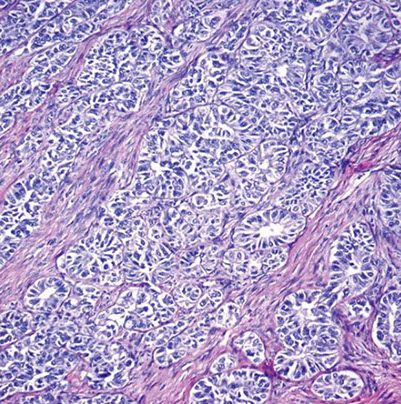

Endometrioid (endometrial) carcinoma

aka type I endometrial carcinoma

MCC endometrial ca (4/5), Indolent cancer due to endometrial hyperplasia

- seen post-menopause white women, after complex atypical hyperplasia, assoc c hormone replacement (E without the P)

Micro: em glands back-to-back >0.2 x 0.2 cm, papillary pattern extensive, or infiltrating irregular glands c desmoplastic or fibroblastic stromal rxn (though this may be reactive... be careful)

- rounded glands have mild-mod atypica c pseudostratification

- can see mucinous differentiation, necrosis in the glands, ciliated cells, and foamy histiocytes in the stroma

Endometrioid carcinoma, FIGO grade 1

Histology and immunohistochemistry of endometrial endometrioid carcinoma. Endometrial endometrioid carcinoma shows a glandular growth pattern (A and B), a wild-type p53 expression (C), patchy p16 staining (D), diffuse nuclear staining for estrogen receptor (E) and progesterone receptor (F), focal nuclear positivity for HNF-1b (G), and negativity for napsin A (H) [3].